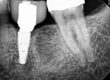

The patient presented on referral for retrieval of a fractured abutment from a 4.8 Straumann BL RC implant in the #18 site. This restoration was placed approximately 10 months ago and although the restoration was not available to examine it appeared, from the radiograph and the clinical presentation, this was a fractured TiBase abutment. There were at least two attempts to recover the abutment fragment, including needle nose pliers, Cavitron ultrasonics and endo ice. In a conversation with the Straumann rep., it was suggested this fragment might be “cold welded”. Generally, recovering RC abutment fragments is not challenging as the abutment connection is basically a slip fit joint (Straumann calls it the cross-fit connection) and above the cross-fit connection there is a top lead in bevel which is .7mm in vertical height, with a 15-degree taper. Recovering this case was no exception, and the fragment was recovered with a precision, custom through bore tool using an aggressive “wobbling” technique. Following retrieval, the implant was internally cleaned and found to be free of defects when inspected at 25x with the clinical microscope. The supplied healing abutment was placed finger tight, and the patient was referred back to the referring Dr. for restoration.

The following photographs are included to point out the mechanical “weak link” in the TiBase concept. The vertical cylinder which fractured at the base of the shoulder has a very narrow wall thickness. I have the habit of calculating the surface area of most abutment fractures I recover and the list keeps growing. Therefore, this recovered fractured abutment fragment was measured on my 14” optical comparitor in my machine shop and the area of the fracture was found to be 3.217 sq. mm. (The wall thickness measured .4mm, the outside diameter was 2.96mm, and the inside diameter of the counter bore was 2.16mm) The counter bore can be visualized in both of the photographs below and extends below the implant top. This position does decrease the cross sectional area of the cylinder by about 1.65 sq.mm. (The through bore diameter measured 1.63mm vs the 2.16mm diameter when the fracture is through the counter bore at the implant top).

Actual fractured abutment fragment on an open analog horizontal and oblique views.